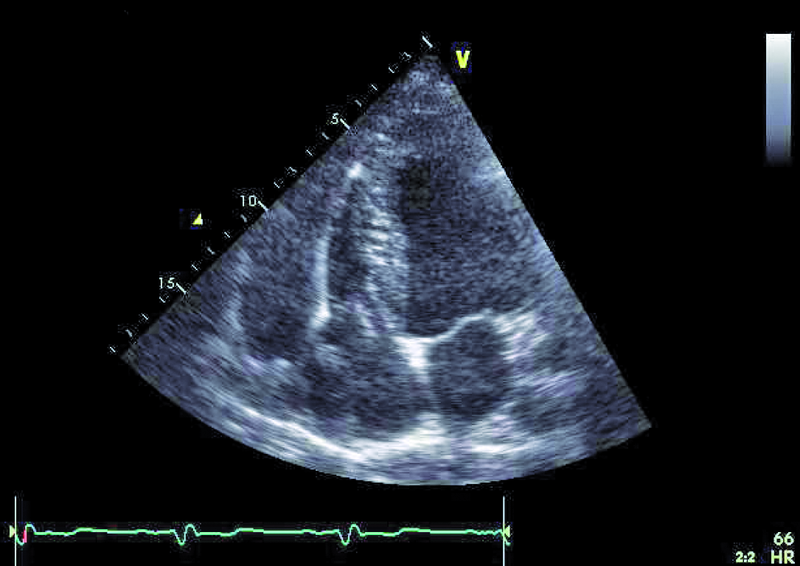

Mężczyzna, lat 25. Jakie patologie można rozpoznać na rycinach?

1. Powiększenie jamy prawej komory (ryc. 1).